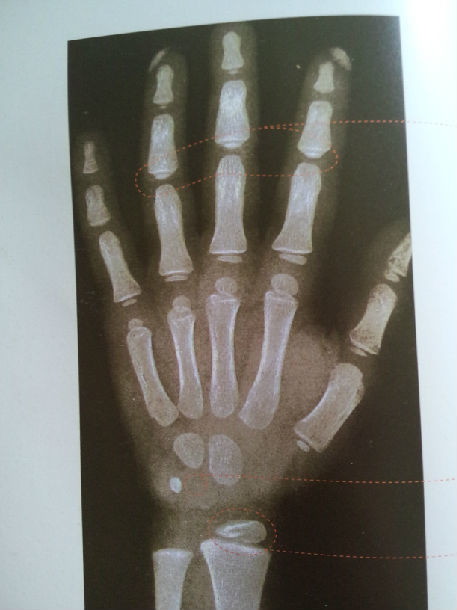

骨龄越小,腕骨数量,密度越小

医生通过x光片观察左手掌指骨,腕骨及桡尺骨下端的骨化中心的发育程度

(图) 腕部正,侧位x线像(11岁)